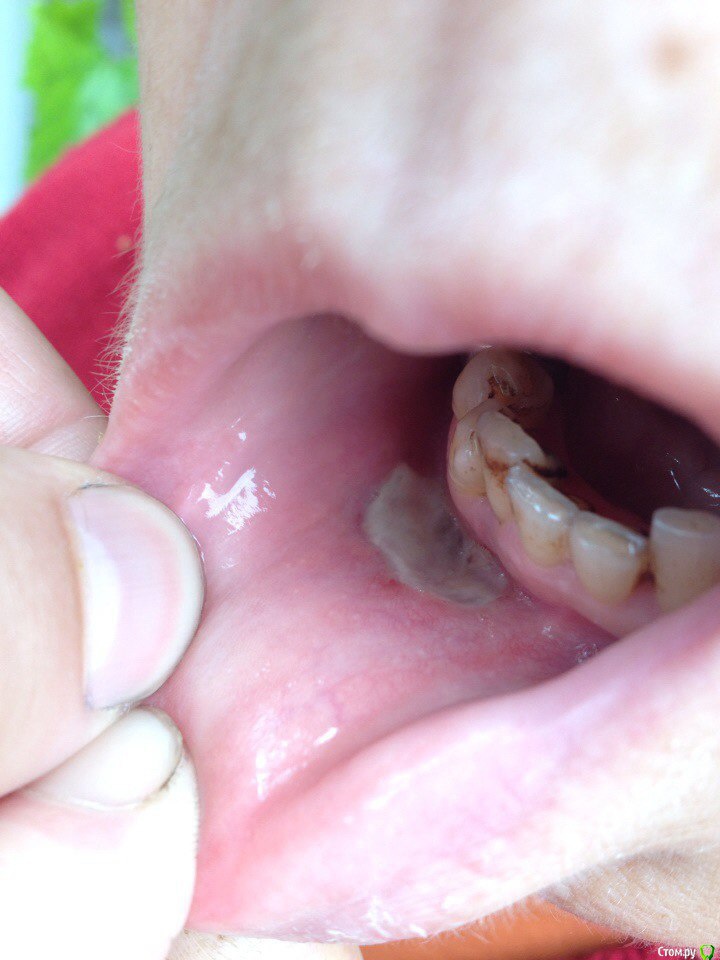

valik_rr Опубликовано 28 июня, 2015 Поделиться Опубликовано 28 июня, 2015 (изменено) Добрый день! Было это все в четверг 25.06.2015 в 9.00 часов.Сделал инфильтрационную анестезию на 42 зуб (пульпит) и случайно эндо иглой вывел гипохлорит 3% мимо канала в мягкие ткани (не заметив как игла ушла мимо канала) была резкая боль затем через 1-2 минуты все прошло) Но немного выпуклая щека! Затем в 16.00 появилась с припухшей щекой и синяком на подбородке и на деснеНазначил антибиотики и НПВП. 2 день утром припухлость была еще больше потом под вечер немного уменьшилась! Сегодня 3 день утром припухлость как и была! вечером припухлость уменьшилась но печет это место на десне! Покрытое якобы беленькой пльоночкою которая флуктуирует при нажатии.Что добавить к лечению ?? Может мазь Солкосерил ???День 4.Сегодня 4 день. Синяка почти нет на подбородке, припухлость тоже сильно уменьшилась. Щека уже холодна, не гарячая так как было. рана зудит!3 первых фото это первый день! И 2 фото 4 день Изменено 28 июня, 2015 пользователем valik_rr Ссылка на комментарий

St. Опубликовано 28 июня, 2015 Поделиться Опубликовано 28 июня, 2015 Нужно добавить полоскания мягкими антисептиками (ромашка, шалфей, ротокан или т.п.).Солкосерил мазь применяется только наружно на кожу. После очищения раны можно назначить солкосерил дентальную адгезивную пасту. 2 Ссылка на комментарий

CRAZYDUCK Опубликовано 28 июня, 2015 Поделиться Опубликовано 28 июня, 2015 Нормальное явление после гипохлорита, такие ожоги болезненные и долго заживают, солкосерил детальная адгезивная паста +1 Ссылка на комментарий